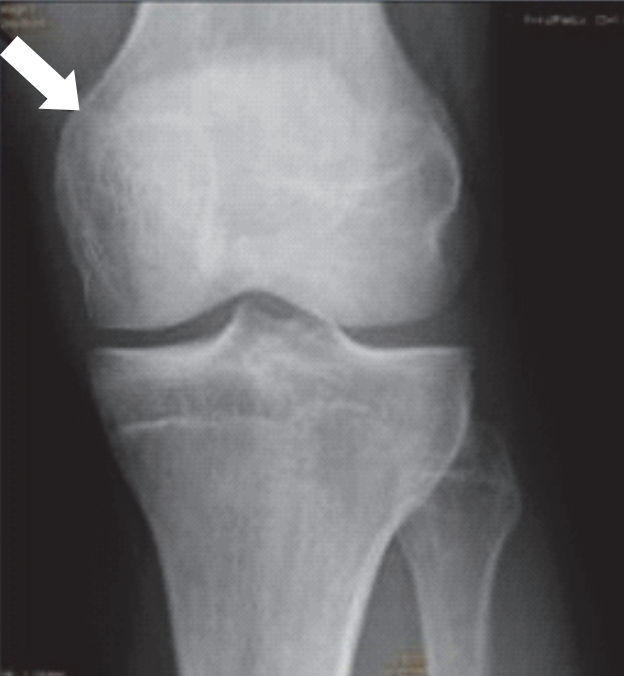

Którą strukturę anatomiczną zaznaczono na radiogramie stawu kolanowego?

A. Nadkłykieć przyśrodkowy.

B. Nadkłykieć boczny.

C. Kłykieć przyśrodkowy.

D. Kłykieć boczny.